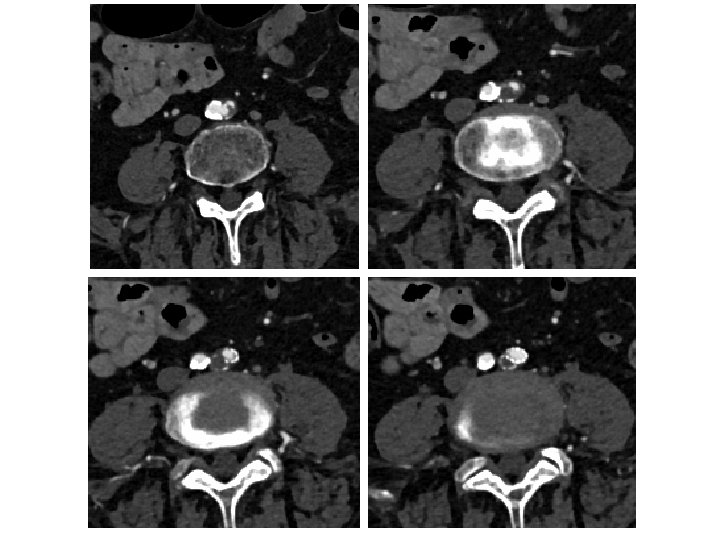

Kissing CBE Stents Still Essential With Distal Aorta Disease • In cases of aortic reentry—kissing stents insure both CIA have adequate flow • The farther the stents extend into the aorta (more that just touching) the more likely they are to narrow/occlude • Kissing Iliac stents should be BE CS (CS>>BMS) Sabri SS, et al. Outcomes of covered kissing stent placement compared with bare metal stent placement in the treatment of atherosclerotic occlusive disease at the aortic bifurcation. J Vasc Interv Radiol. 2010 Jul; 21(7): 995 -1003.